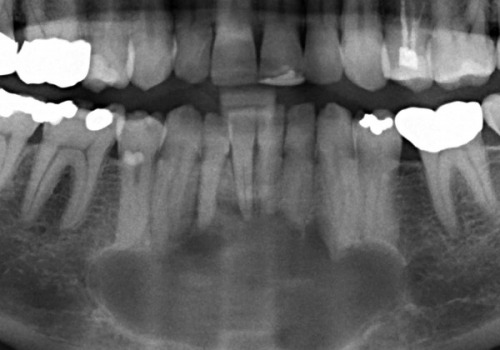

Odontogenik kistlər çənədə ən çox rast gəlinən törəmələrdən olub, başlanğıcını diş orqanından götürür. Bu törəmələr epitel hüceyrə qatı ilə döşənmiş zarla əhatə olunmuş, daxilində isə spesifik maye yerləşən kisəni xatırladırlar. Odontogenik kistlər ya xroniki iltihab nəticəsində ya da inkşaf anomaliyası nəticəsində yarana bilir.

İnkşafı və böyüməsi tədricən baş verdiyindən, bu proses pasiyent tərəfindən demək olar ki hiss edilmir. Yalnız törəmənin ciddi ölçülərə çatması nəticəsində və ya iltihablanması nəticəsində meydana çıxan kliniki əlamətlər nəticəsində aşkarlanır. Əksər hallarda isə çəkilən diş və çənə rentgen şəkillərində təsadüfən rast gəlinir.